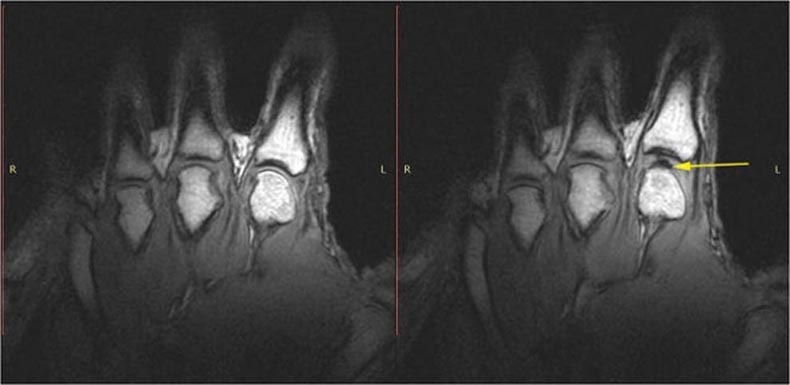

Канадские исследователи при помощи магнитно-резонансной томографии сумели ответить на вопрос, почему раздается хруст, если потянуть за палец руки. На этот раз ученые под руководством профессора Грегори Ковчука (Gregory N. Kawchuk) из Универстита Альберты в Эдмонтоне прибегли к достижениям технологии XXI века. Они соорудили устройство, которое позволяло тянуть за палец в то время, как кисть руки находилась в томографе. Томограф фиксировал процесс со скоростью 3,2 кадра в секунду.

В каждом случае хруст и «расхождение» сустава ассоциировалось с быстрым появлением наполненной газом полости, пузырька в синовиальной жидкости — исключительно скользкой субстанции, которая увлажняет суставы. Когда поверхность сустава внезапно «расходится», жидкости становится недостаточно для заполнения объема сустава, поэтому создается полость, и это приводит к образованию звука.

И его причиной является быстро образующаяся внутри сустава полость. Рабочее название исследования («Потяни меня за палец») отражало его суть — именно так происходило наблюдение, которое фиксировалось с помощью МРТ и показывало, что происходит внутри суставов. Для поиска ответов группе иссследователей нужен был кто-то, кто мог бы хрустеть костяшками по заказу, поскольку большинство людей, которые в состоянии «хрустеть», не всегда могут извлекать хруст из всех пальцев и после стандартной передышки делать это снова. Пальцы испытуемого поочередно помещались в трубку, соединенную с кабелем, который слегка натягивали до хруста в суставе. Хруст фиксировался на МРТ в режиме реального времени и происходил через каждые 310 миллисекунд.